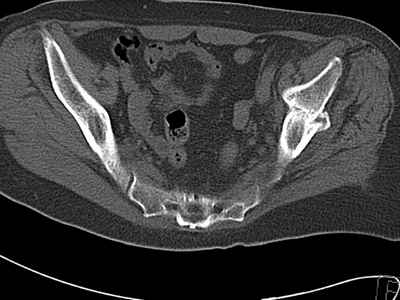

Уважаемые коллеги, возник вопрос по лечению нашей пациентки 60 лет. Около года назад множественная травма: в том числе Т-образный перелом вертлужной впадины. На сегодняшний день сращение отломков имеется на ограниченных участках, имеется дефект задней колонны вертлужной впадины. Движения неплохие, ходит с костылями, приступая на ногу. По мнению эдопротезистов при установке антипротрузионного кольца или октопуса не хватит костного материала и необходимо перед протезированием выполнить реконструкцию впадины, иначе чашка протеза неминуемо выпадет.Просьбы поделиться положительным и отрицательным опытом протезирования в подобных случаях.Возможно ли обойтись без реконструкции?Или лучше с ней?С уважением РАВ.